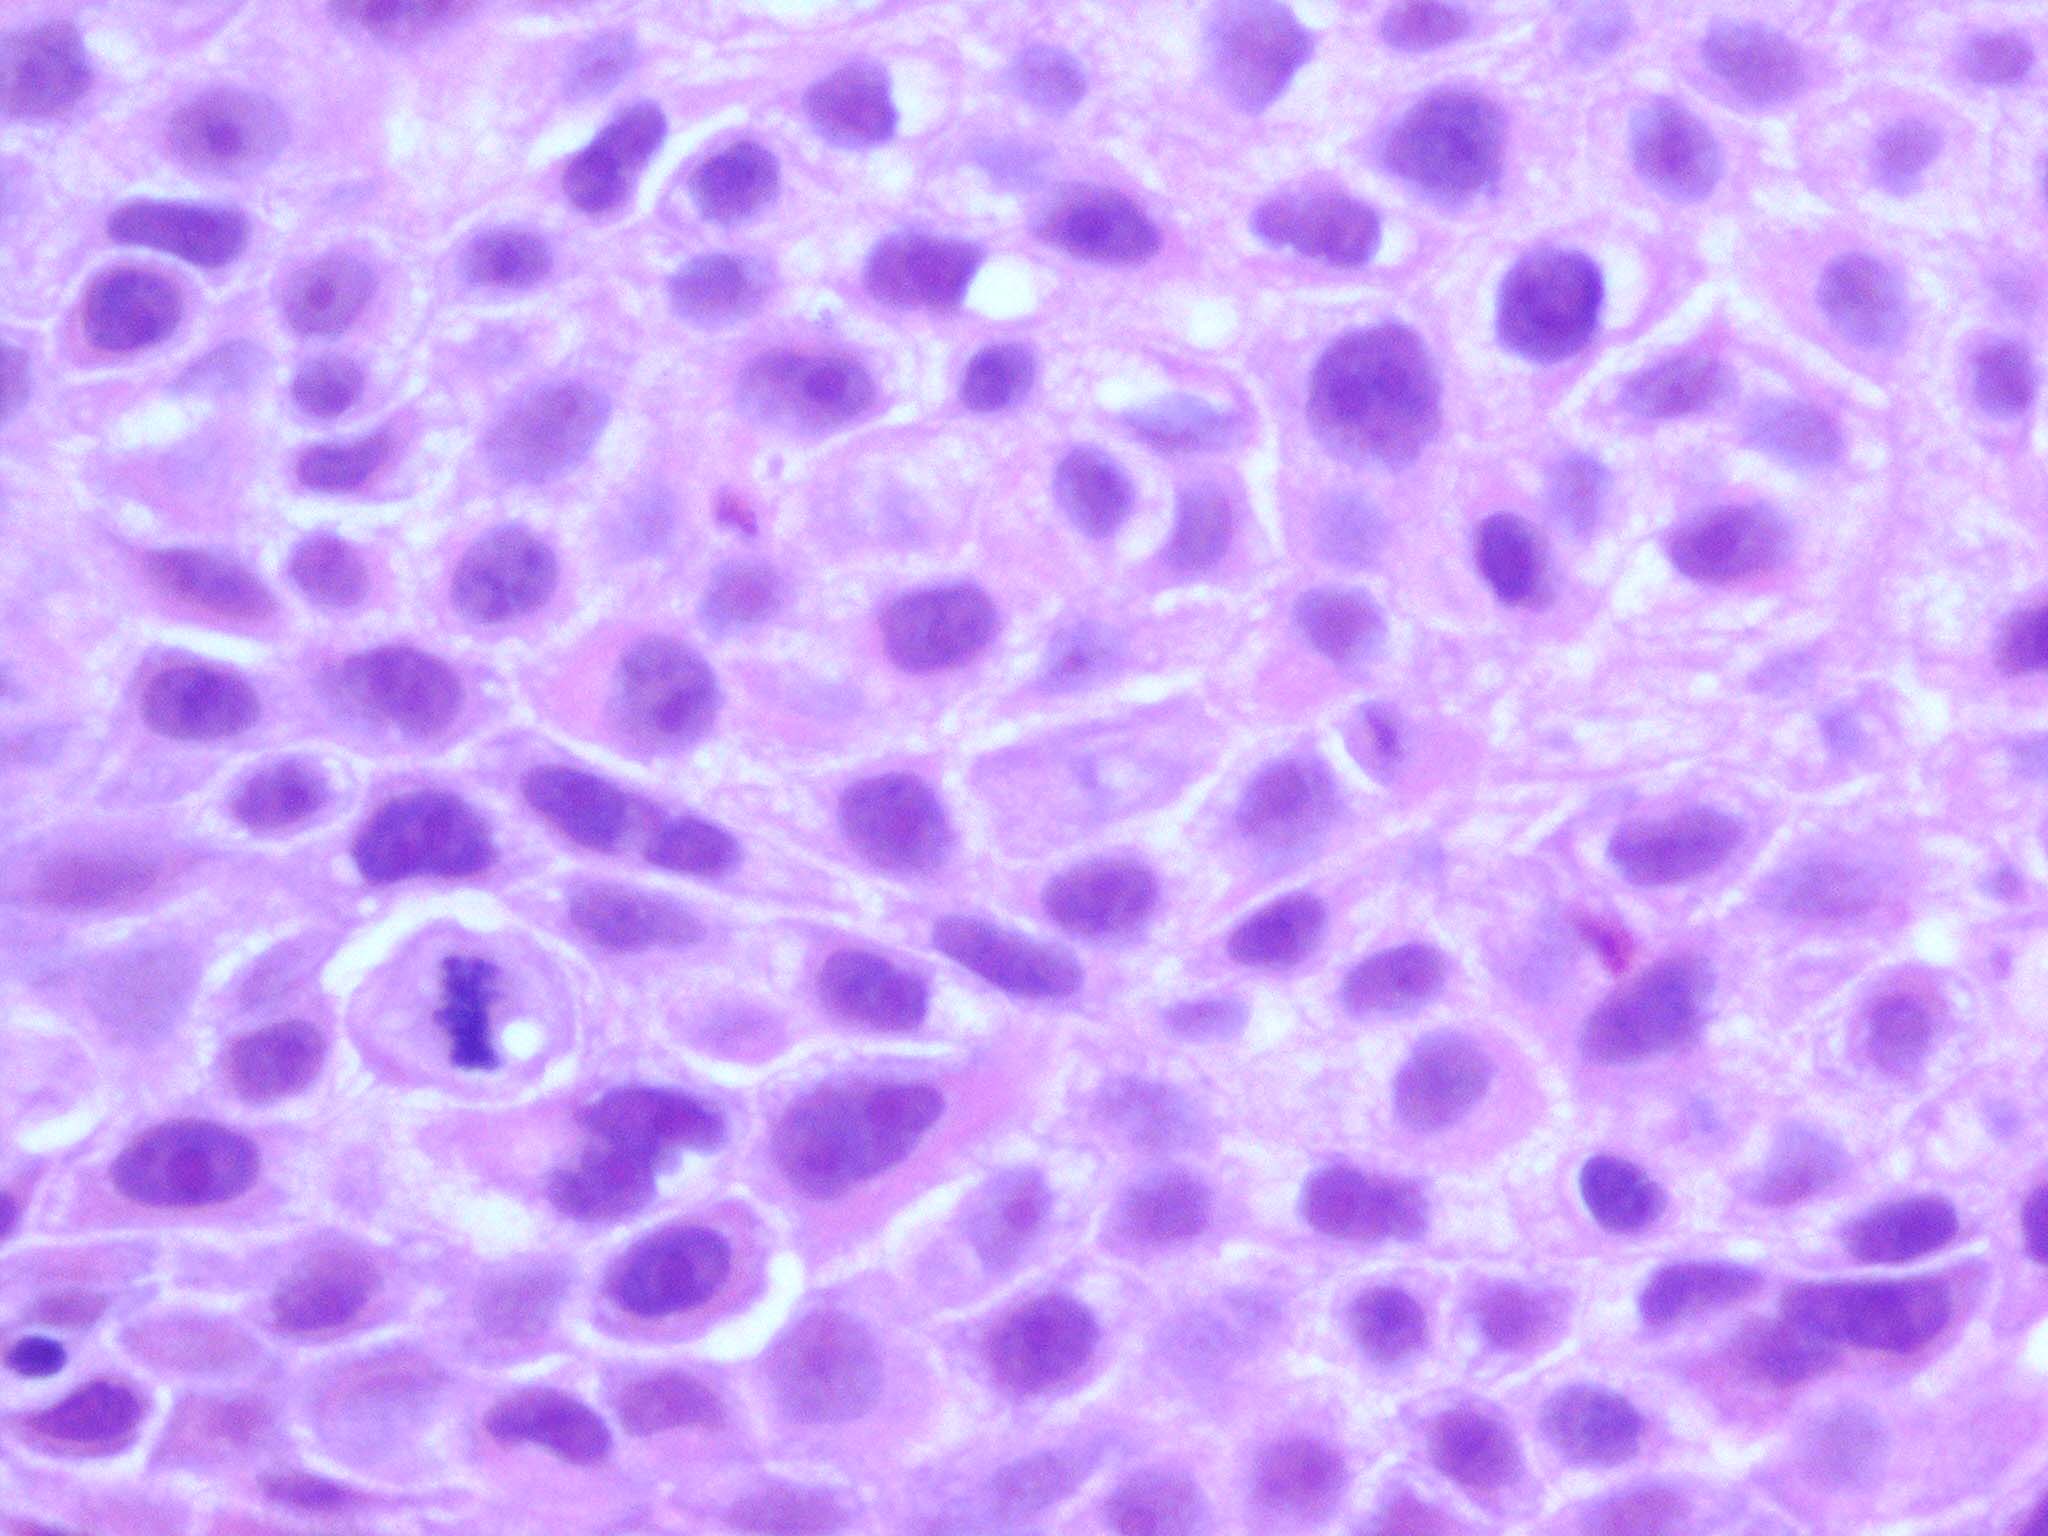

Intraepidermal eccrine carcinoma = الكارسينوما الناتحة داخل البشرة

OLYMPUS DIGITAL CAMERA